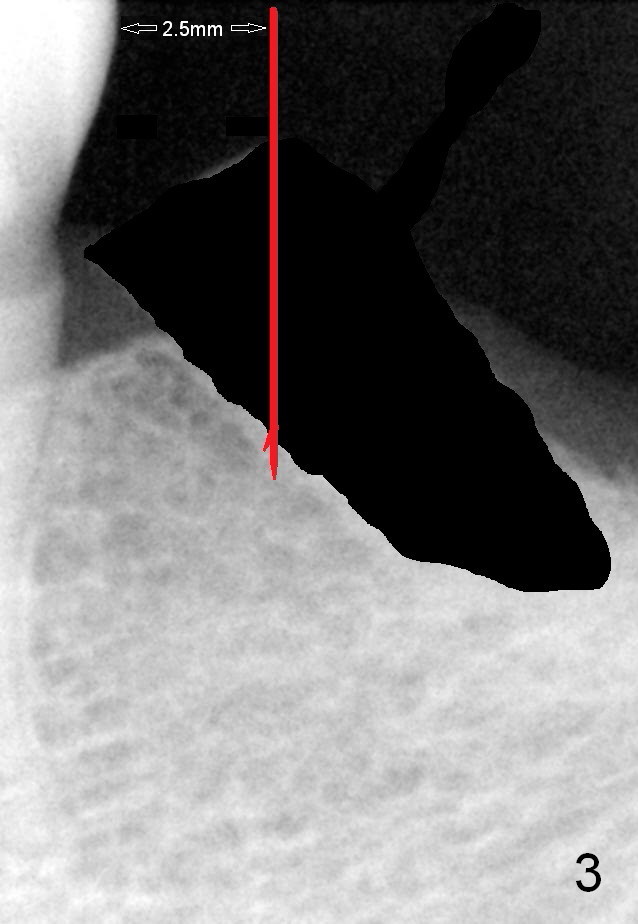

A 78-year-old lady is scared of dentistry, but she has no problem having a 2nd immediate implant (#20 in Fig.1) once the 1st one turns out to be without pain. The challenge associated with #20 is its long axis. After extraction, the osteotomy is initiated in the mesial socket wall at the junction of the upper and middle 1/3 obliquely (Fig.2, slightly lingually). Once the entry is obtained, the axis of the pilot drill is changed to be parallel to the neighboring tooth (Fig.3); an implant spacer of 2.5 mm is used to check (against the 2 mm pilot drill) so that the center of the osteotomy is 3.5 mm from the neighboring tooth (Fig.4). The implant will be 4.5x14 mm. The depth is not longer than that of the neighboring tooth so that it should be quite safe relative to the Mental Loop and the Inferior Alveolar Canal (yellow dashed line in Fig.1). The apical socket is packed with collagen dressing while the coronal one with bone graft. An immediate provisional will be fabricated to keep the graft in place. The osteotomy should be as lingual as possible to avoid the Mental Loop (Fig.1' red dashed line).